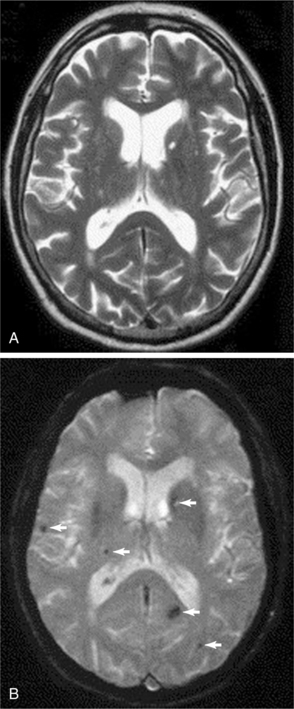

Neuroimaging of the brain has become a standard procedure in the diagnosis of stroke. Computed tomographic (CT) scan is the fastest, most convenient and widely available test to use for the diagnosis and early treatment of acute stroke. It can confirm the diagnosis and rule out other pathologies and extent of the lesion. Fig. 32-12 shows how an acute stroke looks on CT. However, CT scans may be normal in the acute stage of an embolic stroke. Bleeding into the brain tissue is seen acutely in a hemorrhagic stroke. Displacement of brain structures, such as the ventricles, by edema sometimes can be seen early in a large infarct. In ischemic stroke, CT scans reveal the area of decreased density and loss of grey/white matter differentiation resulting from edema. Cortical lesions appear wedge shaped and deeper lesions appear to be round or oval. Potential for hemorrhagic transformation of the ischemic infarct can be seen on CT.75 Lacunar infarcts are sometimes visible on CT scans as small, punched-out, hypodense areas. Images of lacunae and be seen in Fig. 32-13. Identification of the penumbra and infarct core on hyperacute noncontrast and perfusion CT may lead to potentially more aggressive treatments related to reperfusion and to arrest progression of stroke damage in the early part of the stroke.74 Fig. 32-14 demonstrates how the use of new imaging techniques may assist in this goal.

Figure 32-13 In these images, the left side of the brain is on the right of the panel. Axial T2-weighted fast spin-echo sequence (A) and corresponding axial T2*-weighted gradient echo sequence (B) from a 57-year-old man who presented with a left lacunar syndrome; his risk factors included hypertension and smoking. The T2-weighted fast spin-echo sequence shows several hyperintense foci in the cerebral white matter and basal ganglia but no microbleeds. The T2*-weighted gradient echo image shows several areas of focal signal loss consistent with microbleeds (arrows) in the right frontal lobe, right thalamus, left parietal lobe, and left caudate nucleus. (Reprinted from Werring DJ, et al: Cerebral microbleeds are common in ischemic stroke but rare in TIA, Neurology 65(12):1914-1918, 2005.)